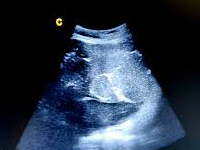

38-letnia pacjentka z gruczolakorakiem torbielowatym wątroby

38-year-old patient with cystadenocarcinoma of the liver

SurgeryCystadenocarcinoma is a rare malignant liver tumor that arises de novo or from benign lesions of the nature of cystadenocarcinomas. Symptoms are nonspecific and include: pain in the right upper quadrant of the abdominal cavity, a feeling of discomfort or fullness, jaundice, weight loss and are related related to the size of the lesion. The recommended treatment is resection of the lesion along with a margin of healthy tissue.